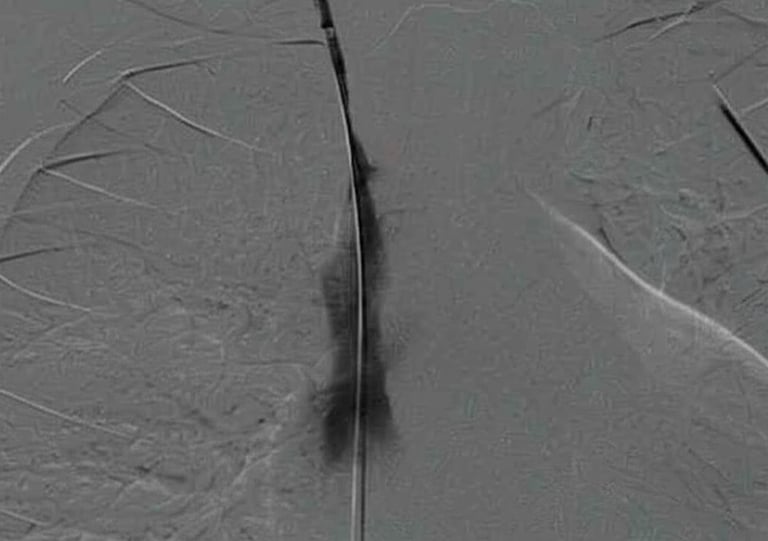

Paso de guía Amplatz Super Stiff por zona de estenosis dentro de la vaina de fibrina